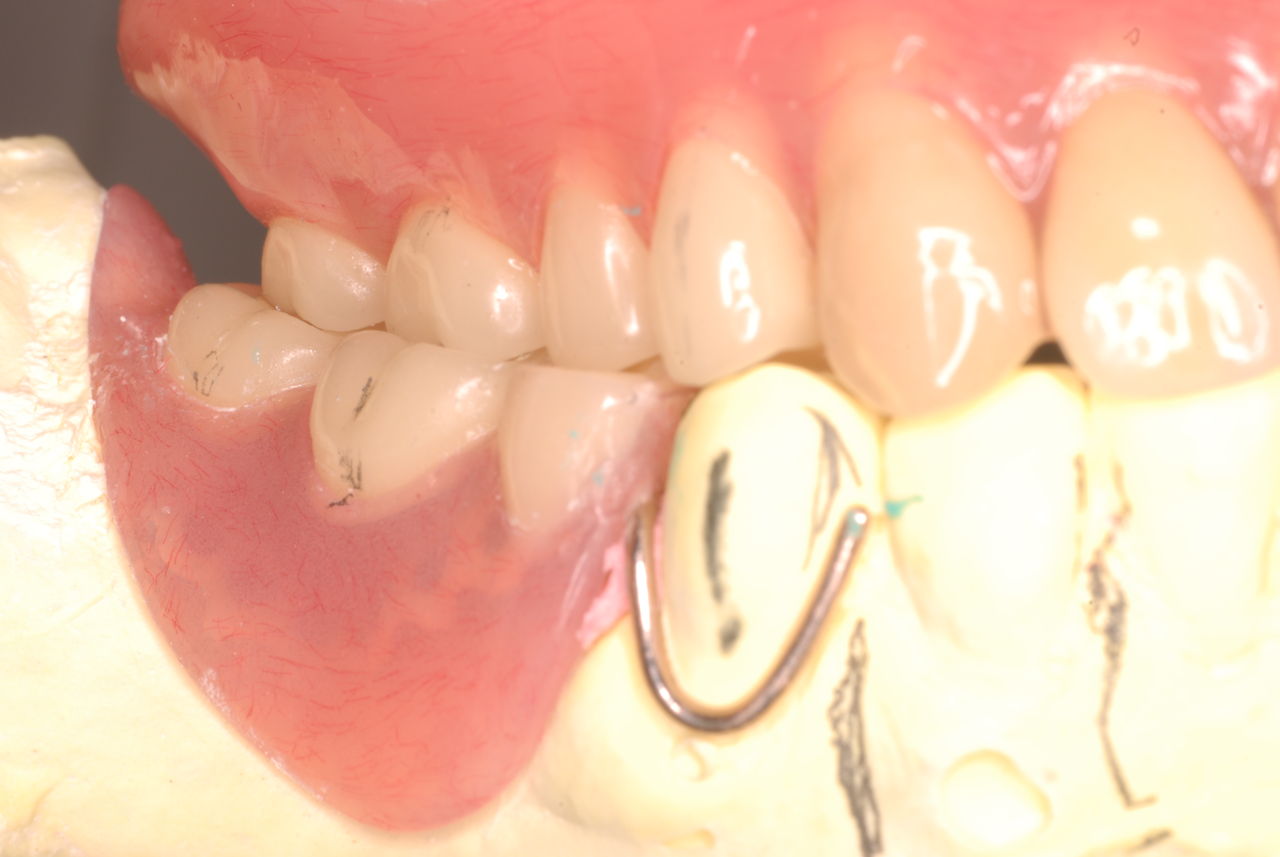

上の総義歯はまっったくはずれませんでした。下顎の入れ歯では若干痛みが出そうなので噛み合わせの調整をしています。口腔内では時間がかかりすぎるので器械に付けて調整しています。

下顎が右にシフトしているので噛み合わせはとても慎重にしました。下の方が頬側にないと安定せず噛めないのです。

左側の噛み合わせはまともにできます。